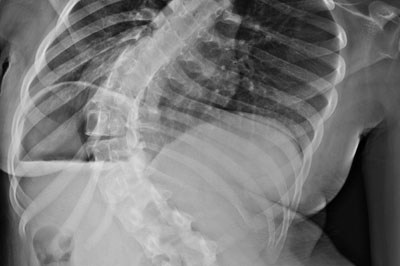

Spinal deformity

spinal-deformity

Any alteration in the normal shape of the spinal column is called as spinal deformity. If it is abnormal lateral bending of the spine it is called as scoliosis...

• Spinal deformity - scoliosis, kyphosis and congenital spinal problems